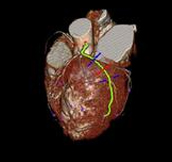

picture acquired together with electrocardiogram data. ECG triggering both retrospective and prospective mode possible.

MPRs performed at oblique planes to the body or the coronary arteries.